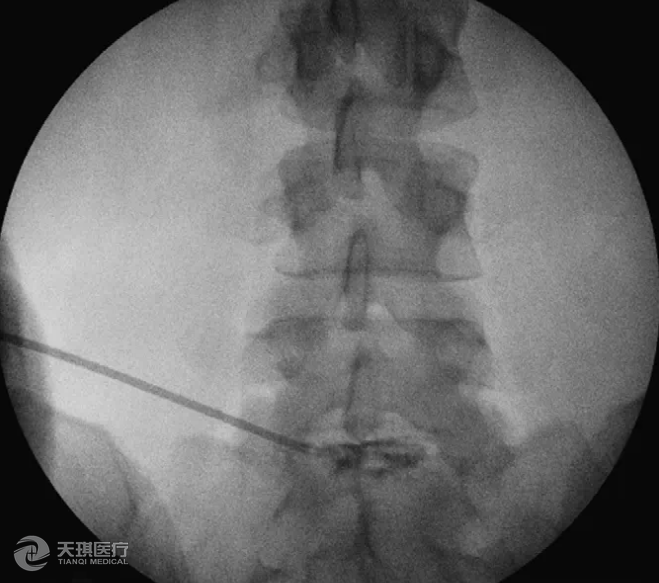

如果患者不能行MRI檢查(例如患者裝有起搏器),CT或脊髓造影可作為替代檢查。椎間盤造影在復雜病例中也可以幫助診斷(圖5)。

圖5 當鑒別腰椎神經根性病變是某個間盤所引起時,椎間盤造影可以幫助診斷。